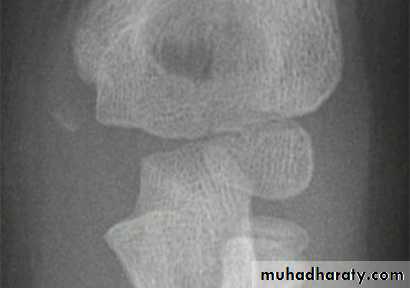

This fracture occur due to fall on out stretched hands . The fracture piece although it look small in the x-ray but it in fact is large and it pulled by extensor muscle of the wrist which attached to it .In sever cases the piece is rotated by the action of the extensor muscle and become capsized lead to nonunion later on if not treated .

Clinically :

The elbow swollen and deformed , tenderness at the site of the fracture .

Treatment :

If there is no or minimal displacement we can do back slab above the elbow which is 90` flexed and the forearm is neutral ; after 7 days repeat the x-ray for checking and full p.o.p. for 3-4 weeks , followed by active physiotherapy .

Displaced fracture need open reduction and fixation by K-wire or screw